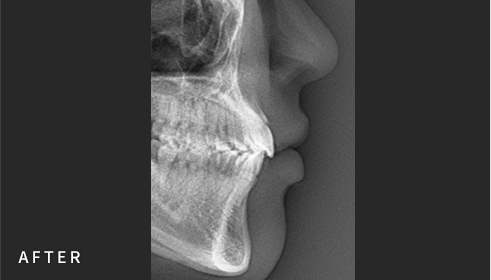

• Cephalometric X-ray 촬영

2~3초의 짧은 시간 안에

얼굴의 측면 엑스레이 촬영이 가능합니다.